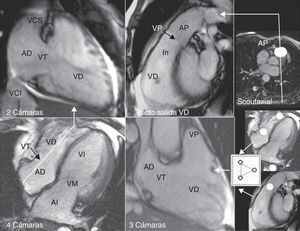

Los planos «básicos» para estudiar el VD en RM son el 4 cámaras (4C) y el eje corto (EC), que se obtienen de manera rutinaria en cualquier protocolo de RM cardíaca. Cuando la sospecha clínica apunta al VD, es conveniente disponer de planos específicos (fig. 1): dos cámaras derechas (2CD), tres cámaras derechas (3CD o entrada-salida del VD,) y tracto de salida del VD (TSVD). Las imágenes axiales (doble IR y cine) con menor campo de visión consiguen mayor resolución espacial de la pared libre del VD, lo cual puede ser útil en la displasia arritmogénica del VD (DAVD).

Planos empleados en RM para estudiar el ventrículo derecho: 4 cámaras, 2 cámaras derechas, 3 cámaras derechas y tracto de salida del ventrículo derecho (AD: aurícula derecha; AI: aurícula izquierda; AP: arteria pulmonar; In: infundíbulo; VD: ventrículo derecho; VCI: vena cava inferior; VCS: vena cava superior; VI: ventrículo izquierdo; VM: válvula mitral; VP: válvula pulmonar; VT: válvula tricúspide).